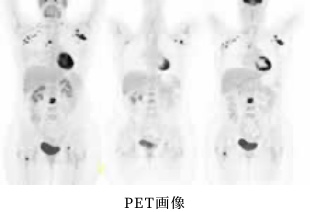

PET-CT検査について

東海大学医学部付属病院にある

PET/CT装置を利用し、検査を行います。

PET/CTとは?

PETとは、がん細胞が正常の細胞に比べて多くのブドウ糖を取り込むという性質を利用して、ぶどう糖に放射線を放出する物質を付けた薬剤(放射性薬剤)である18F-FDGを用いた、核医学検査の一種です。放射性薬剤を体内に投与し、画像化します。それにCTを組み合わせた検査がPET/CT検査です。PETによるぶどう糖代謝などの機能情報とCTによる臓器のかたちを画像化する形態情報の両面から病気を発見することが出来ます。 PET/CT検査では、頭部から膝上までの全身を一度に調べます。